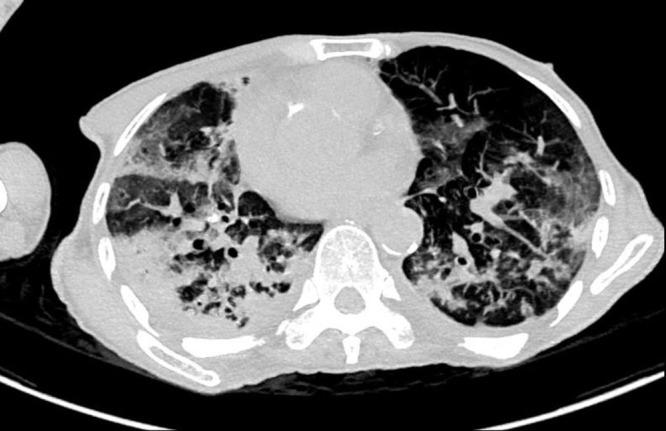

Herpes simplex virus type 1 (HSV1) pneumonia presents diagnostic challenges due to there being no gold-standard criteria currently. Specimens from bronchoalveolar lavage can increase specificity, and cytohistological examination can prove virus infection. Patients with high viral load have been reported with poor outcomes and benefited from antiviral agent. We describe an 80-year-old man with severe pneumonia who initially showed improvement without antiviral therapy, despite viral inclusion bodies on sputum cytology and positive HSV1 polymerase chain reaction from sputum, though subsequent clinical deterioration due to infection necessitated intensive care. This case highlights the complexities of diagnosing and managing HSV1 pneumonia, emphasizing the importance of integrating clinical suspicion, radiological imaging, and laboratory tests for timely therapeutic decisions in critically ill patients.

由于目前尚无金标准诊断标准,1型单纯疱疹病毒(HSV1)肺炎的诊断面临挑战。支气管肺泡灌洗标本可提高特异性,细胞组织学检查可证实病毒感染。据报道,病毒载量高的患者预后较差,抗病毒药物治疗有益。我们描述了一名80岁的重症肺炎男性患者,尽管痰细胞学检查发现病毒包涵体且痰HSV1聚合酶链反应呈阳性,但最初未接受抗病毒治疗时病情有所改善,不过随后因感染导致临床病情恶化,需要重症监护。该病例凸显了HSV1肺炎诊断和管理的复杂性,强调了在重症患者中综合临床怀疑、影像学检查和实验室检查以做出及时治疗决策的重要性。